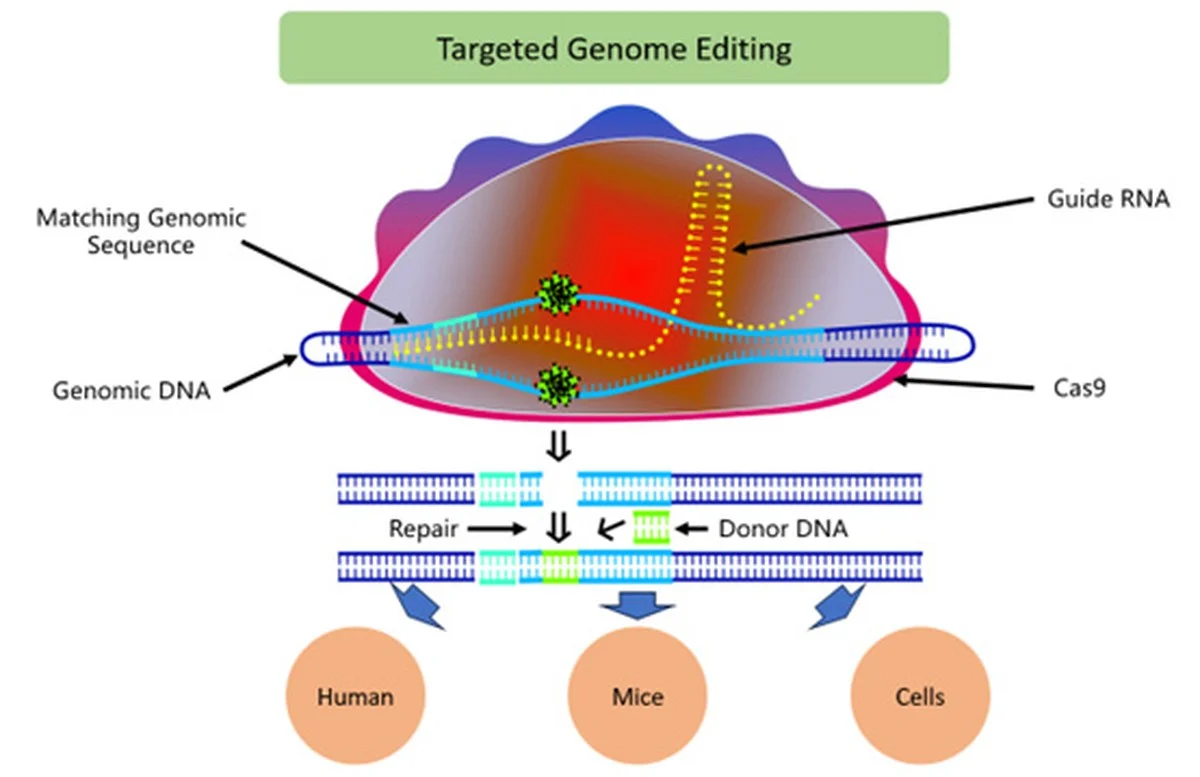

Hier kommt der Clou: Mittels CRISPR-Technologie haben die Forscher einen „Schalter“ in das REC8-Protein eingebaut. Wenn dieser Schalter betätigt wird, zersetzt sich das Protein gezielt und kontrolliert. Das ist der Geniestreich.

- Präzision, die früher fehlte: Frühere Methoden waren ungenau. Jetzt können Forscher den exakten Schwächegrad des Klebstoffs steuern.

- Die Grenze der Belastbarkeit: Man konnte exakt bestimmen, ab welchem Punkt des Kontrollverlusts die Chromosomenfehler exponentiell ansteigen.

- Keine lange Wartezeit mehr: Was Jahrzehnte dauert, wird zum einstündigen Laborexperiment.